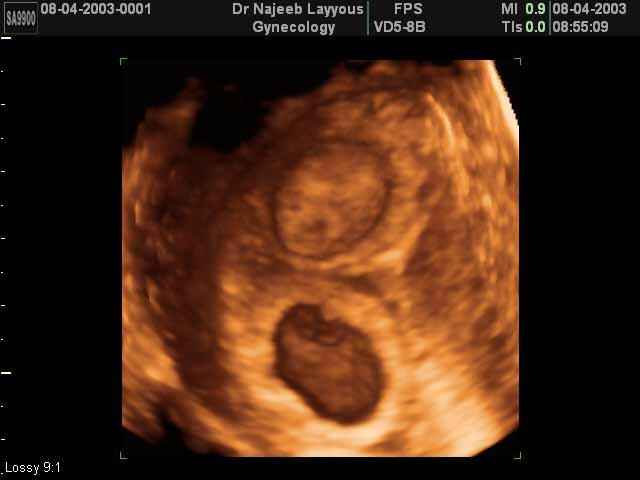

- لقطات فيديو للجنين بجهاز الموجات فوق صوتية رباعي الأبعاد

- صور للجنين في المراحل الأولى من الحمل

- صور لتوائم

صور لتوائم بجهاز الالتراساوند ثلاثي الأبعاد | الدكتور نجيب ليوس